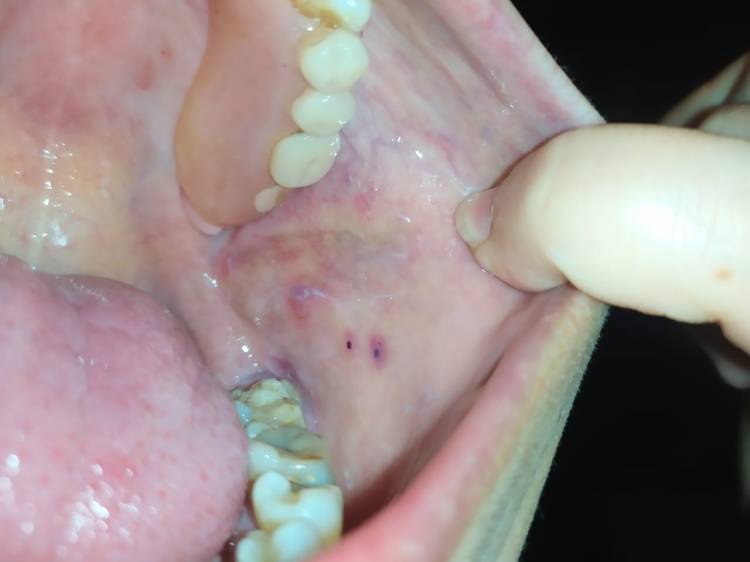

Puntos hemorrágicos